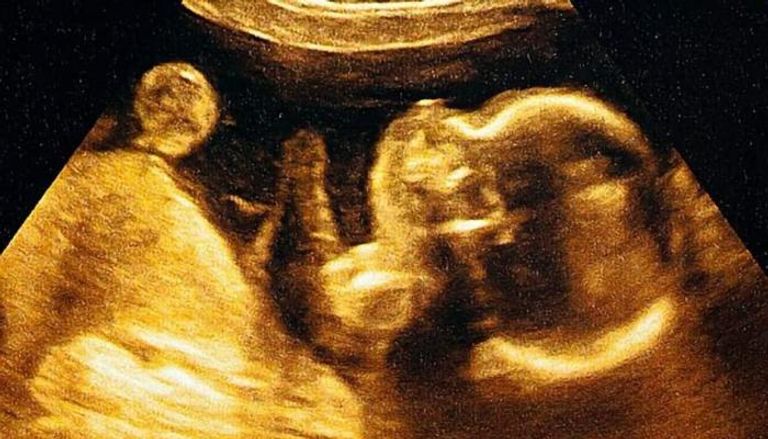

لكن مجموعة من الباحثين الأميركيين تقول إن استخدام الذكاء الاصطناعي لتحليل صور الموجات فوق الصوتية يمكن أن يتنبأ بموعد ميلاد الطفل بدقة تصل إلى 95 في المئة.

وباستخدام برنامج تم تطويره وتدريبه باستخدام أكثر من مليوني صورة بالموجات فوق الصوتية لنساء أنجبن أطفالهن بين عامي 2017 و2020، قام العلماء بقياس مدى قدرة الذكاء الاصطناعي على تقدير ما إذا كان الطفل سيرى النور في موعد ولادته أم لا.

التنبؤ بموعد ولادة الطفل في حالة الحمل المكتمل بدقة بلغت 95 في المئة.

التنبؤ بالولادة المبكرة بدقة بلغت 72 في المئة، من دون الحاجة إلى بيانات إضافية مثل التاريخ الطبي للأم أو القياسات السريرية.

التنبؤ بجميع حالات الولادة (بما في ذلك المبكرة) بدقة وصلت إلى 92 في المئة.